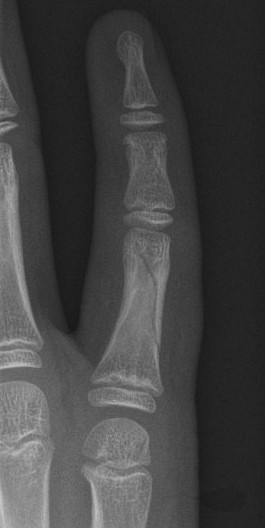

Mallet finger

Volar plate injury

- Dorsal blocking splint and follow up with plastic surgery clinic in 1-2 days